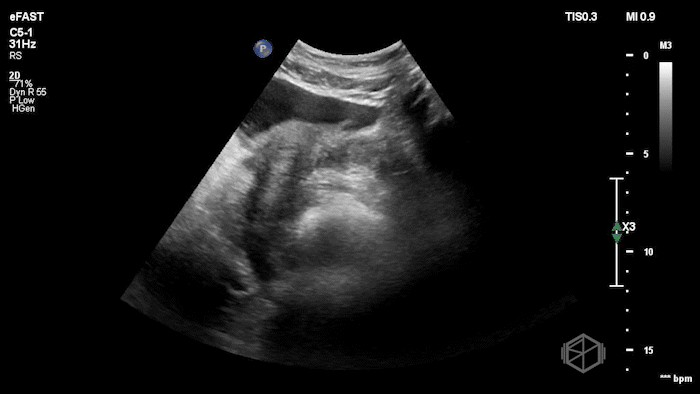

Drs. Ariz and Scavelli were caring for an approximately 40-year-old woman, G2P1, at approximately 8 weeks gestation, who presented to the ED with abdominal cramping. She was hypotensive on arrival, prompting the team to reach for the ultrasound immediately. They saw the following:

POCUS showed free fluid throughout the abdomen, including the RUQ, LUQ, and pelvis. The uterus was empty, and the final clip appears to show a complex left adnexal mass.

Diagnosis: Left ectopic pregnancy with hemoperitoneum